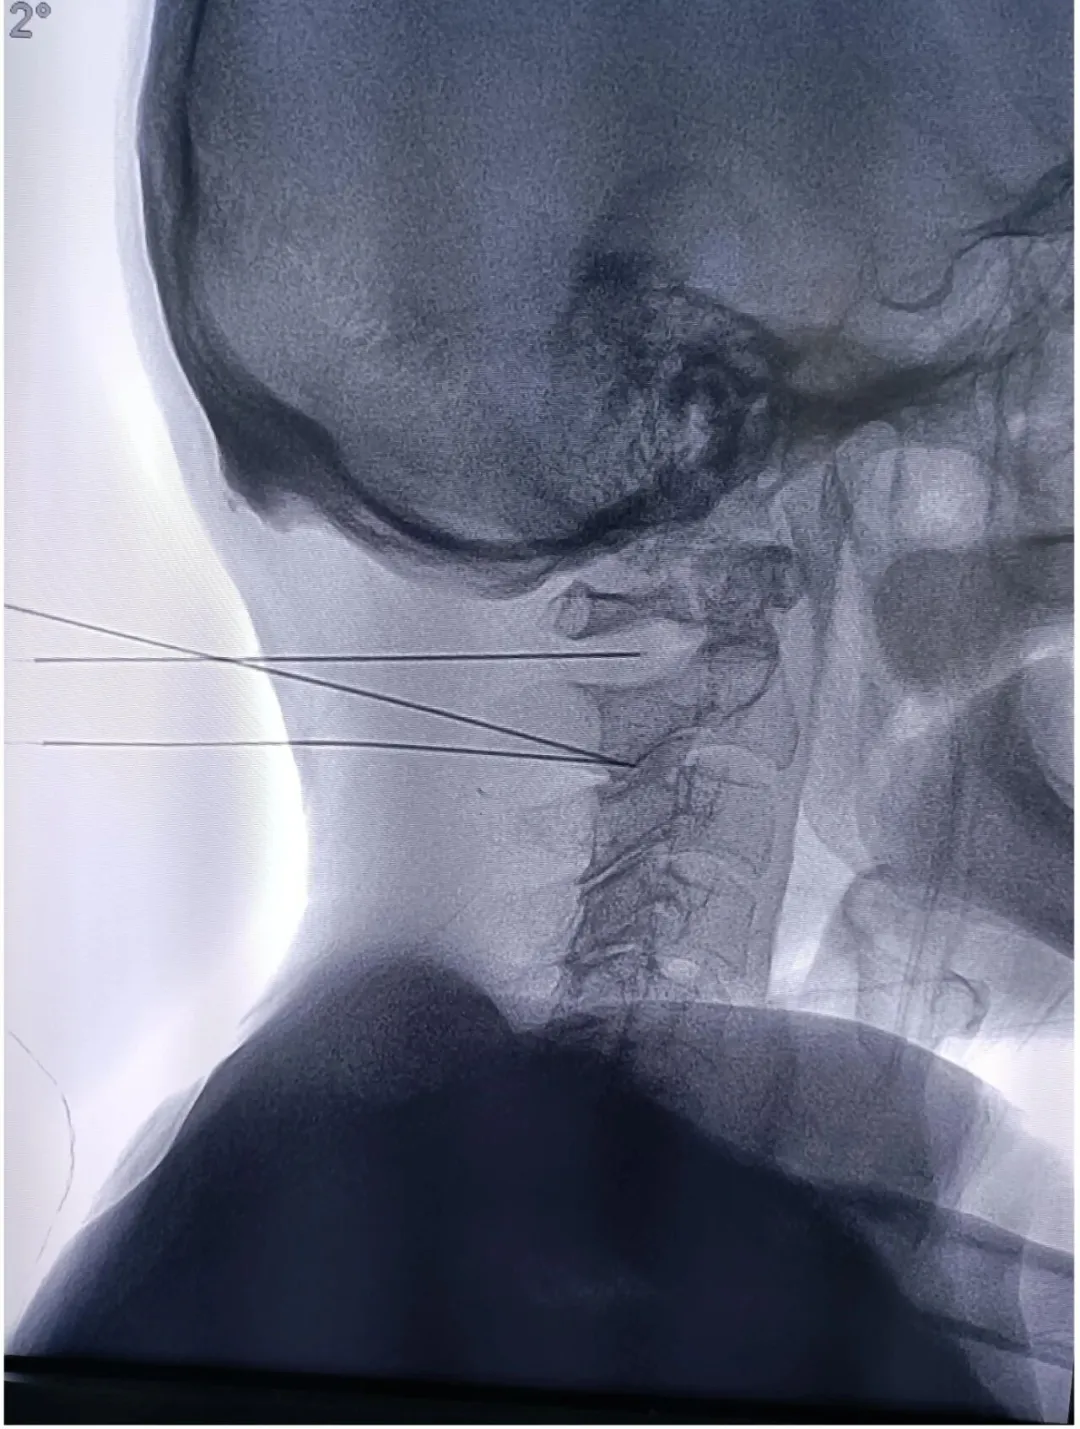

六、脊髓神经电刺激植入术

脊髓神经电刺激植入术是指将脊髓刺激电极置于椎管的硬膜外腔后间隙,刺激电极产生电场,刺激脊髓后部的上行结构:脊神经背根、脊髓后角神经元、脊髓丘脑束等,通过电流刺激脊髓后柱的传导束和后角感觉神经元,阻断/干扰疼痛信号通过脊髓向大脑传递,从而达到治疗疼痛或其它疾病目的的一种治疗方法。电刺激植入的适应症: 复杂性局灶性疼痛综合征(CRPS) 、神经源性疼痛(神经病理性疼痛) 、幻肢痛/残肢痛、带状疱疹后遗神经痛、脊髓损伤 、 糖尿病周围神经痛、周围缺血性疼痛 、血栓闭塞性脉管炎、糖尿病足等慢性疼痛。

神经电刺激术的优点: